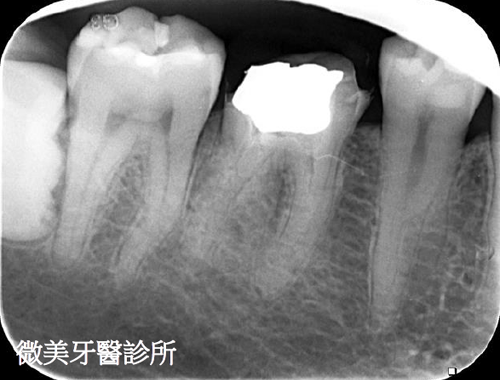

根管鈣化阻塞,利用顯微鏡搭配器械完成多根管治療

原先根管治療未完整,利用顯微鏡重新根管治療,達到多根管封填